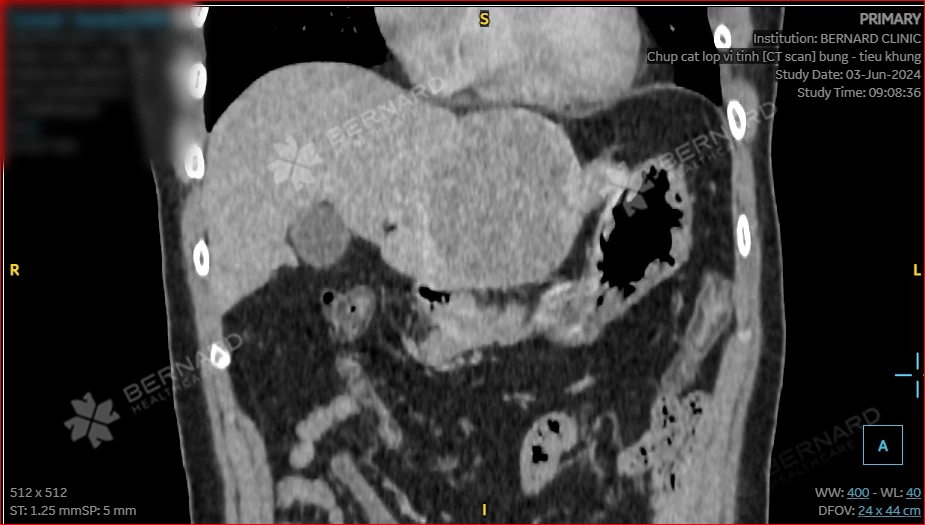

Ảnh chụp CT Scan của anh T. cho thấy, vùng bụng có những tổn thương choán chỗ lớn ở nhu mô gan trái, hạ phân thùy II, III và một phần IV, kích thước khoảng 75x85x82mm, đậm độ thấp trên phim, bắt thuốc tương phản mạnh không đồng nhất, có vỏ bao thì muộn. Ngoài ra, còn có một nang gan nhỏ ở vùng hạ phân đoạn VIII, kích thước khoảng 5mm.

Từ kết quả này, các bác sĩ đã đưa ra nhận định: Bệnh nhân mắc UNG THƯ BIỂU MÔ TẾ BÀO GAN (HCC). Tuy nhiên, cần thực hiện thêm các xét nghiệm để chẩn đoán phân biệt với ung thư tế bào gan dạng xơ dẹt (FLC).